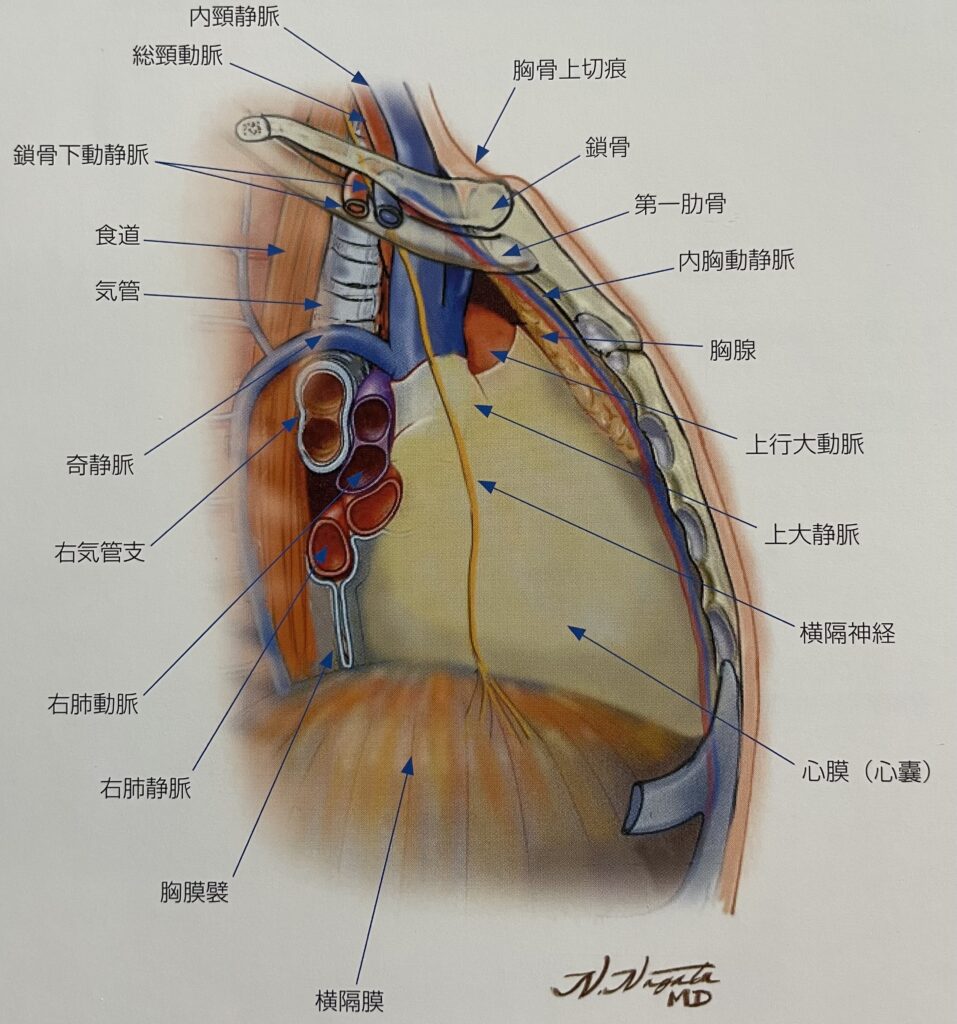

呼吸器系2,3-呼吸解剖1,2。縦隔腫瘍について | 新座志木中央総合病院。縦隔腫瘍|がん診療の特色と実績(院内がん登録)|診療体制。桂新堂 海老 えび せんべい。

※個人情報の記載がある場合は、サインペン等で塗りつぶした上で発送させていただきます。胸腺腫(きょうせんしゅ Thymoma) – 呼吸器疾患 - 神戸きしだ。

【送料】商品毎に記載あり。南山堂 / 外科学一般 / 呼吸器外科学。